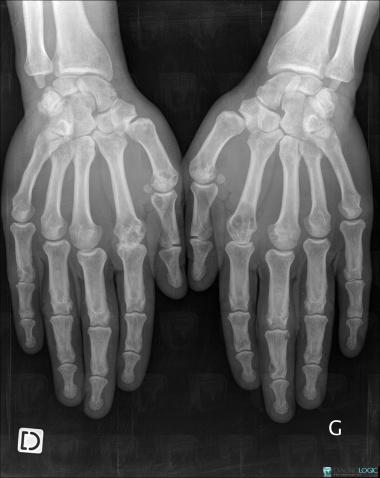

Sarcoïdose, Métacarpiens, Phalanges / Os sésamoides - Main, Radio

- Diagnostic Sarcoïdose, Localisation(s) Métacarpiens, comportant les gammes Lésion ostéolytique des os de la mainArticulations métacarpo phalangiennes, comportant les gammes Arthropathie sans ostéoporoseArticulations inter phalangiennes - Main, comportant les gammes Arthropathie sans ostéoporosePhalanges / Os sésamoides - Main, comportant les gammes Ostéolyse phalangienne